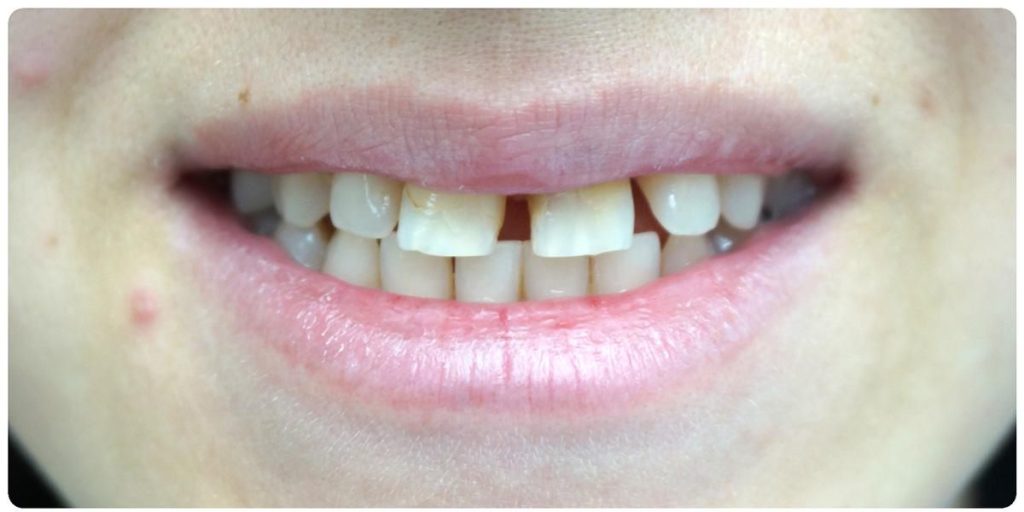

Przypadek Pacjentki:

- Pacjentka nie miała zawiązków górnych dwójek.

- Wszczepiliśmy implant w miejsce górnej dwójki.

- Przeprowadziliśmy wybielanie zębów, aby uzyskać idealny odcień.

- Wykonaliśmy pełnoceramiczne licówki na górne jedynki.

- Zmieniliśmy wygląd kła przy pomocy licówki, aby wyglądał jak naturalna dwójka.

Całe leczenie trwało tylko 3 miesiące, a efekt końcowy przeszedł najśmielsze oczekiwania.

Licówki i korona na implancie wykonane przez laboratorium Dentalscan.